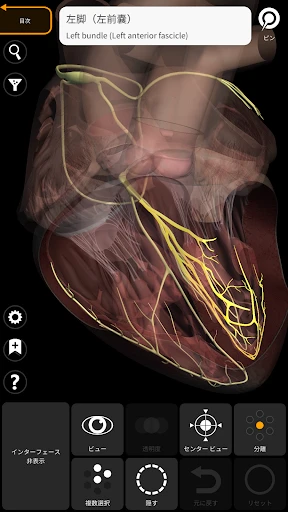

皆さん、3Dで人体を探検したことはありますか?このアプリを使うと、まるで本物の標本を手に取っているかのように、人体の構造を詳細に観察できます。何よりも嬉しいのは、非常にリアルなグラフィックスです。3Dモデルはとても精密で、筋肉や骨、内臓の位置関係が一目瞭然です。

さて、ここで気になるのは使いやすさですよね。ご安心ください!インターフェースは直感的で、スムーズに操作できます。ピンチでズームイン・アウトしたり、スワイプで回転させたりと、直感的なジェスチャーで操作可能です。このあたりは、スマホやタブレットでの操作に慣れている方なら、すぐに使いこなせるはずです。

この「解剖学 - 3Dアトラス」、ただのビジュアルツールにとどまりません。かなり多くの情報が詰まっています。例えば、各部位の詳細な説明や、医学用語の解説も充実しているので、学習にはもってこいです。特に、試験勉強中の学生さんには非常に役立つことでしょう。

私のお気に入りの機能の一つは、特定の部位を選択すると、その部位に関する詳細な情報が表示されることです。これにより、単なるビジュアルだけでなく、知識を深めることができるのです。